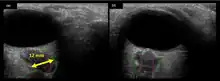

The astronauts affected by long term visual changes and prolonged intracranial hypertension have all been male, and SOS may explain this because in men, the sternocleidomastoid muscle is typically thicker than in women and may contribute to more compression. The reason that SOS does not occur in all individuals may be related to anatomic variations in the internal jugular vein. Ultrasound study has shown that in some individuals, the internal jugular vein is located in a more lateral position to Zone I compression, and therefore not as much compression will occur, allowing continued blood flow.